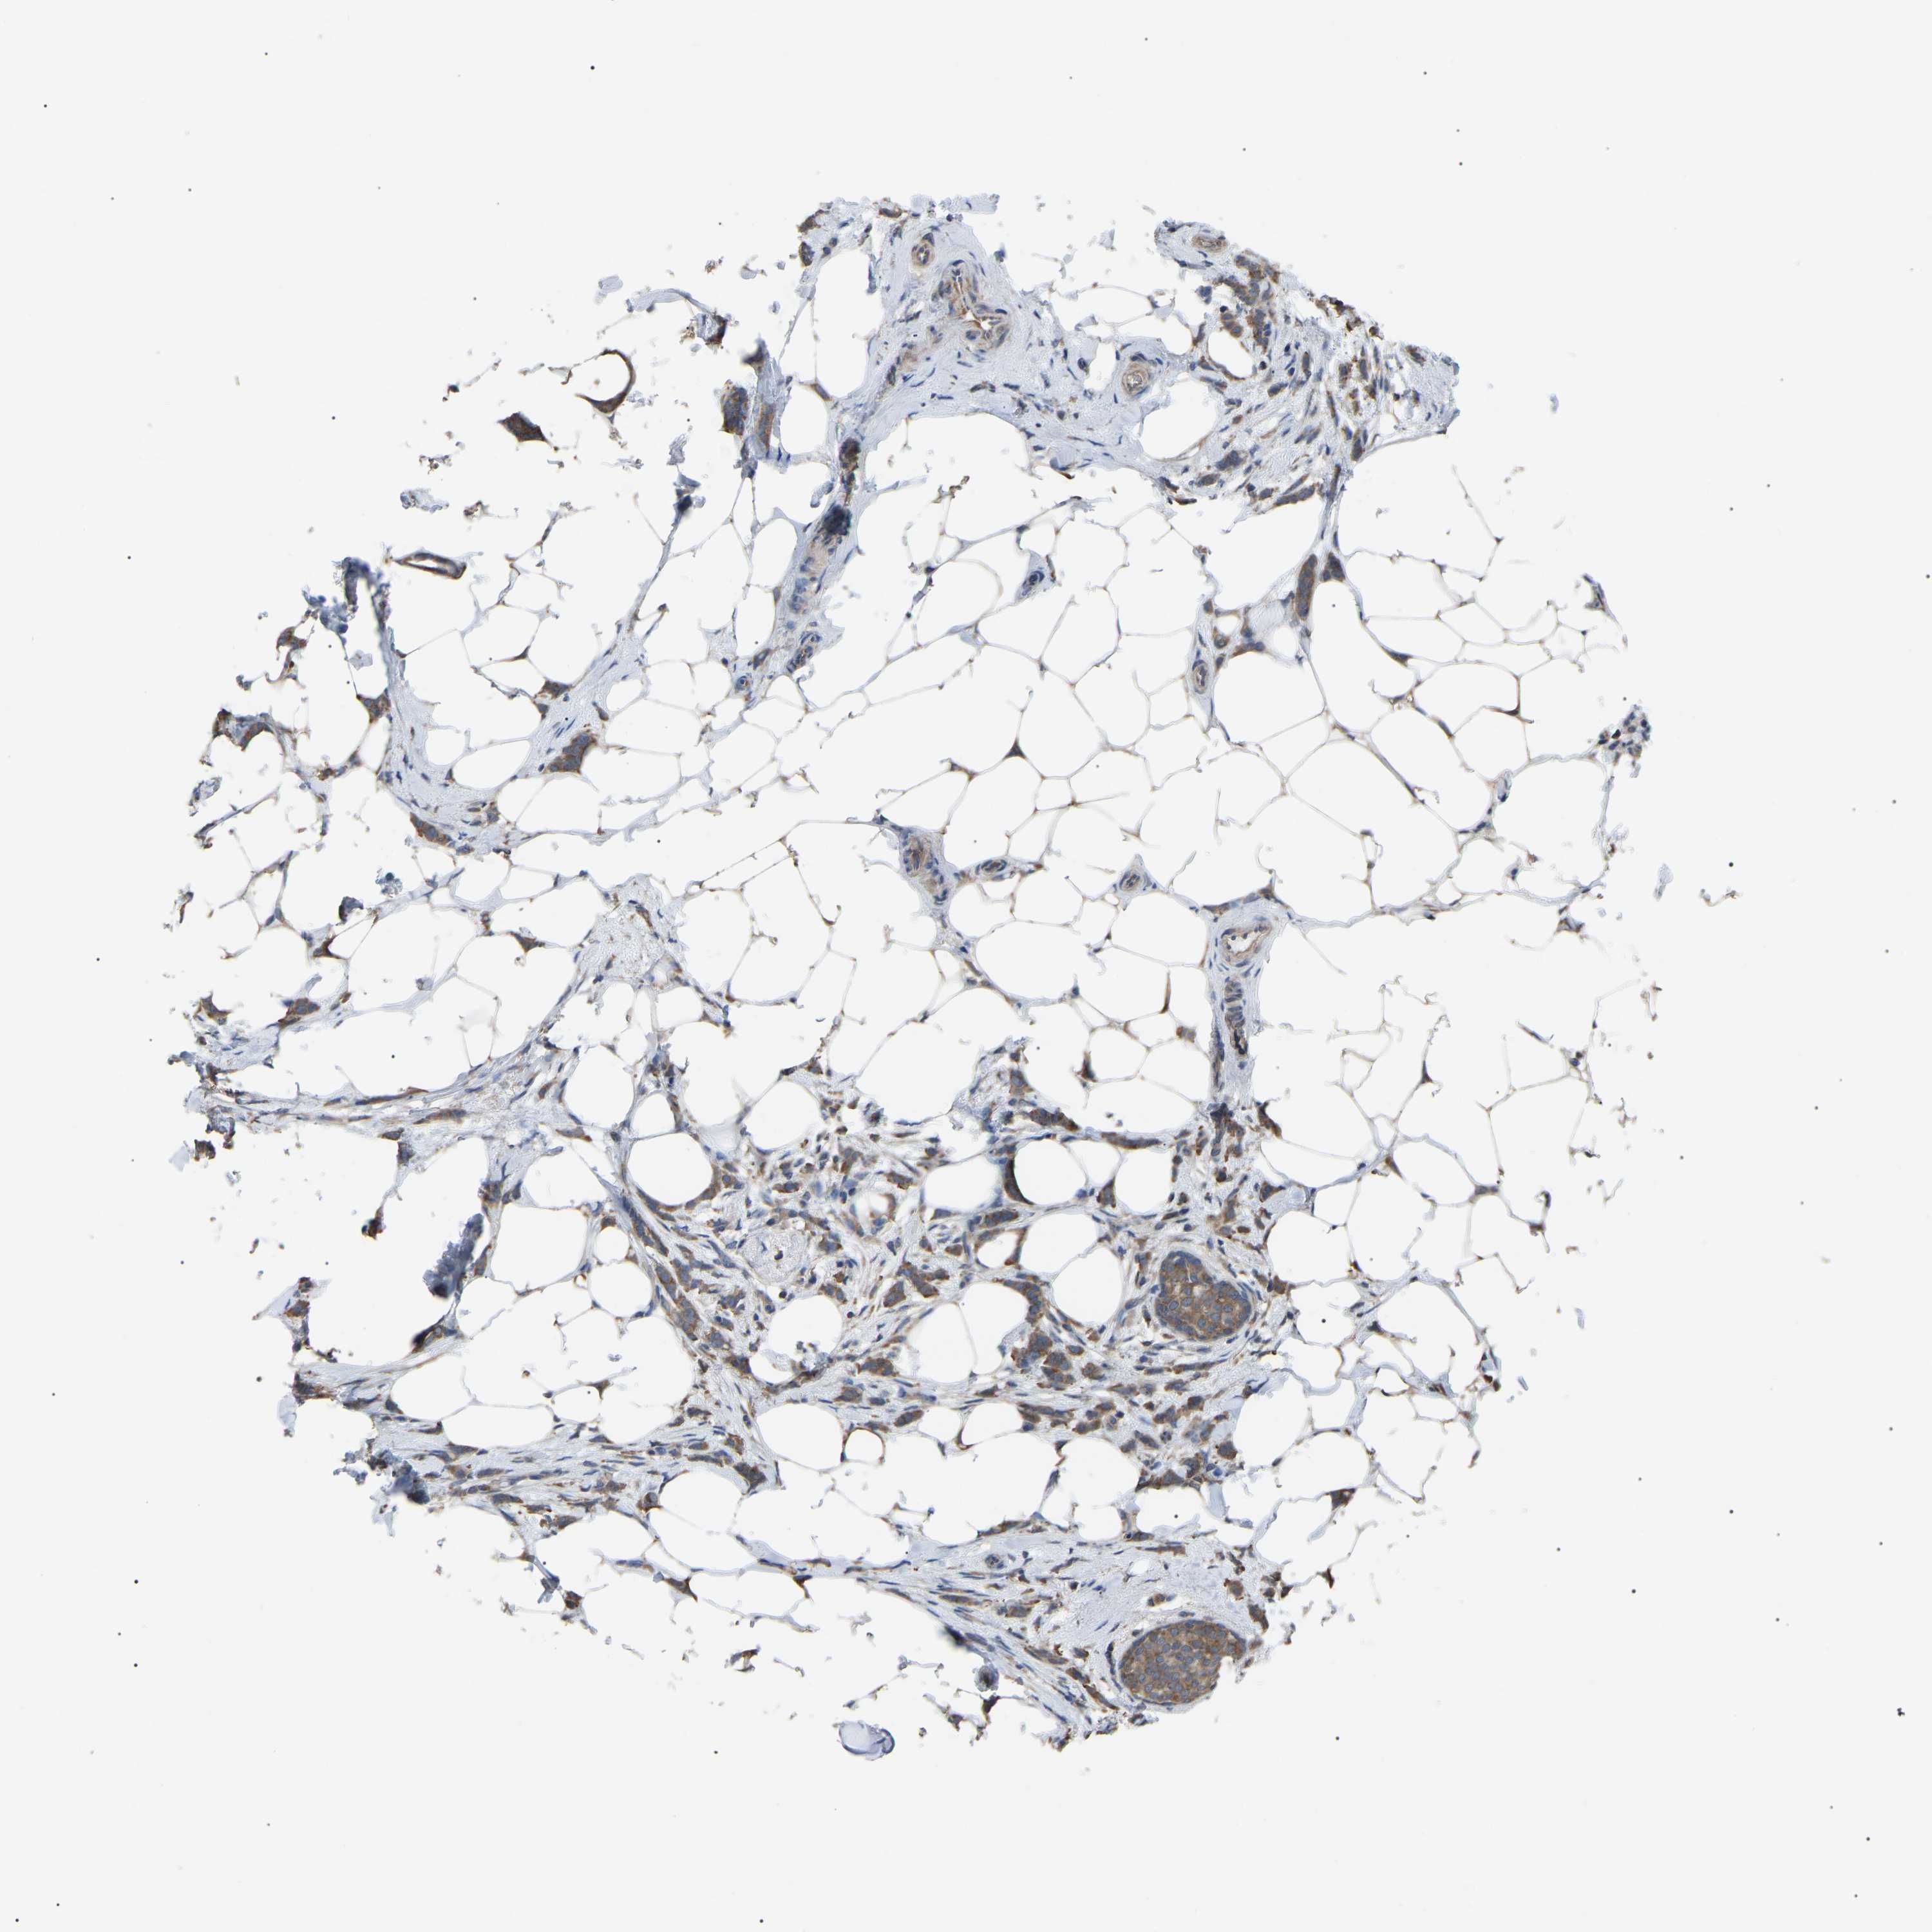

CANCER BREAST CANCER Show tissue menu

BRCA TCGA BRCA VALIDATION PROTEIN EXPRESSION

ANTIBODIES

AND

VALIDATION